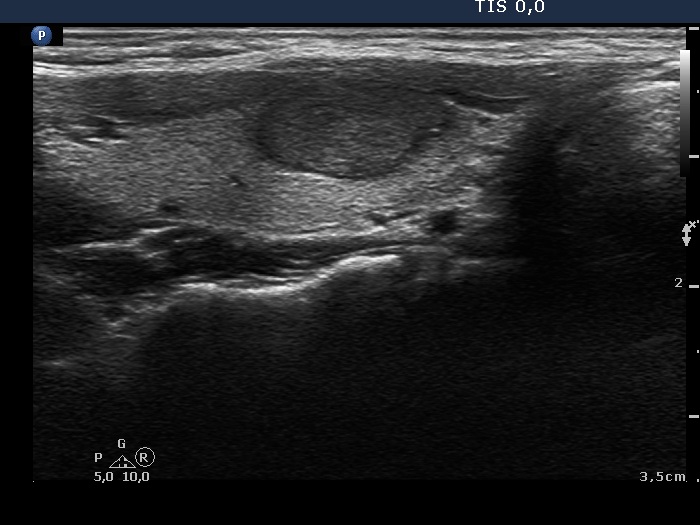

First examination (first row of images)

Clinical data: A 21-year-old woman was referred for evaluation on a nodular goiter. She has noticed an enlargement in the left lobe for a year. On evaluation in another institute, a cystic nodule was diagnosed with a 26 mm maximal diameter and 3 mL brown fluid was aspirated. Cytology resulted in benign cystic lesion.

Palpation: The right lobe was suspicious having a nodule.

Laboratory test: TSH 2.21 mIU/L.

Ultrasonography. The thyroid was echonormal and presented a moderately hypoechoic nodule in the right lobe and a cystic nodule with minimally hypoechoic solid part corresponding to the previously aspirated cystic lesion. The largest diameter of the latter was 11 mm which means that cyst has not refilled. The nodule in the right lobe showed irregular, more hypoechoic areas all along at the periphery. This pattern mimicked halo sign, but indeed the lesion did not have a real halo. The vascularization of the nodule in the right lobe presented an irregularly increased intranodular blood flow while the lesion in the left lobe did signs of perinodular vascularization.

Cytology was performed form the lesion in the right lobe and resulted in follicular proliferation.

Combined ultrasound-cytological diagnosis was benign follicular proliferation.

Suggestion: ultrasound in a year.